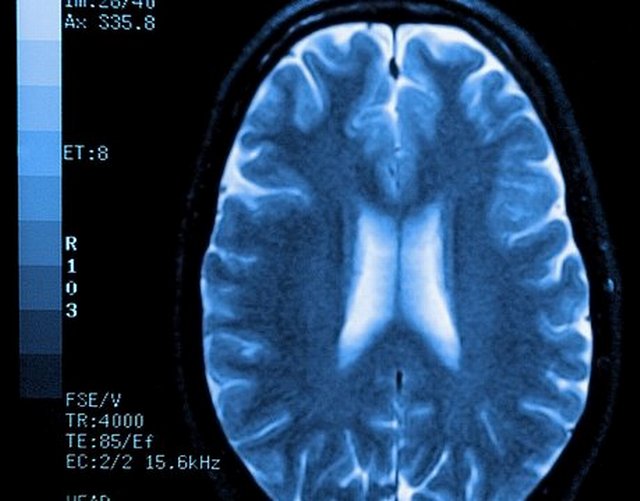

وتعتبر هذه الدراسة الأولى من نوعها (2013) حيث استخدم العلماء التصوير بالرنين المغنطيسي لأدمغة مجموعة من الشباب المدمنين على مشاهدة أفلام الجنس، إن نتائج الدراسة فاجأت العلماء بخطورة المناظر الجنسية، وضرورة الحد من مشاهدتها!!!

تظهر الصور بالمسح بالرنين المغنطيسي أن المنطقة الأمامية تتآكل وتتضرر كثيراً بنتيجة الإدمان على مشاهدة المناظر الجنسية. (المرجع 12). هذه المنطقة عندما تفقد جزءاً منها فإن سلوك الإنسان يضطرب ويفقد توازنه وينقاد وراء شهواته كالمجنون.. وقد ينتحر أو يرتكب جرائم... (المرجع 23).

أظهرت دراسة أجريت عام 2002 على مدمني الكوكائين وجود تلف في بعض أجزاء الدماغ وبخاصة في المنطقة الأمامية، (المرجع 16) كذلك في دراسة عام 2004 تبين أن الدماغ يخسر جزءاً من وزنه بسبب الإدمان على المخدرات (المرجع 17)... ويمكن القول إن نفس الشيء ينطبق على الإدمان على المشاهد الإباحية (المرجع 18).